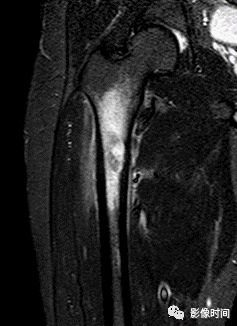

九、瘤周水肿

肿瘤周边的骨髓水肿表现为 T1WT 低信号和 T2WI、STIR 高信号边界模糊的片状影,软组织肿块邻近的正常软组织成分,尤其是肌肉内亦可出现水肿,表现为肿块周围沿肌束方向分布的边界模糊的片状或羽毛状影,有时可连成片。瘤周水肿常见于恶性肿瘤(图 58),但也可见于某些良性肿瘤如软骨母细胞瘤(图 59)、骨样骨瘤和骨嗜酸性肉芽肿(图 60)等。

图 59 瘤周水肿:软骨母细胞瘤